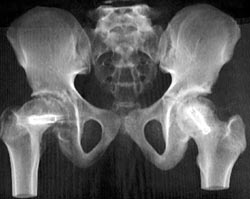

Total Hip Replacement (THR) Without Dislocation